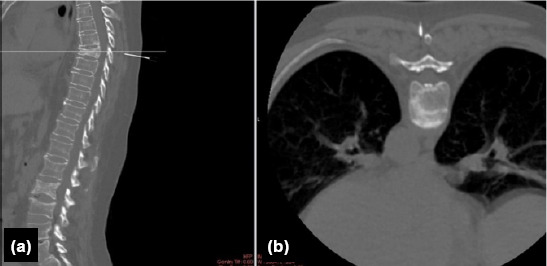

Methods: Fourteen patients undergoing posterior aproach to the thoracic spine and/or spinal cord related lesions were investigated. Spinocaths were placed under CT guidance, into the pedicle of the relevant vertebra, at the same day or the night before surgery. The surgical field is prepared as usual, and a spinocath is placed to the relevant thoracic pedicle under CT guidance.

Results: Intraoperative level localization was more reliable and easier in patients undergoing preoperative CT-guided marking in surgeries on the thoracic region performed for various reasons. Shorter preoperative preparation and intraoperative anesthesia times, a decrease in number of fluoroscopic images taken intraoperatively, and no spinal mislocalizations were observed.